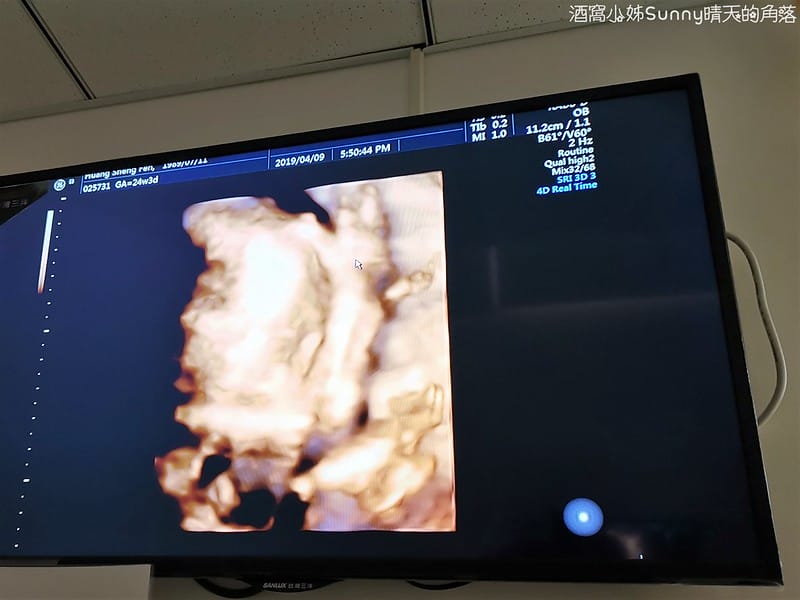

▼答案是:外生殖器,也就是性器官,Abby's二寶是「妹妹」唷~

其實上次產檢就知道是女生,Sunny興奮的在診間叫出聲

大寶是哥哥,二寶是妹妹,Abby好厲害湊成一個『好』字了❤

這是當天妹妹拍到最清楚的4D影像照

▼因為...妹妹全程都用手遮臉,都不給媽咪和阿姨看 >"<